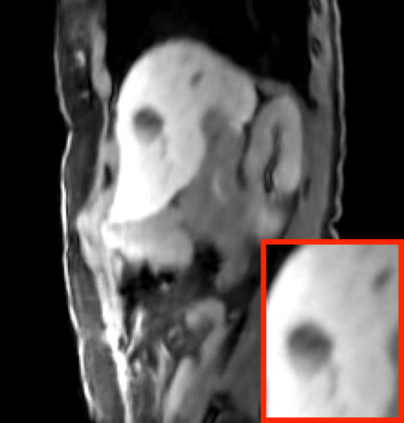

Deep neural networks for medical image reconstruction are traditionally trained using high-quality ground-truth images as training targets. Recent work onNoise2Noise (N2N) has shown the potential of using multiple noisy measurements of the same object as an alternative to having a ground truth. However, existing N2N-based methods cannot exploit information from various motion states, limiting their ability to learn on moving objects. This paper addresses this issue by proposing a novel motion-compensated deep image reconstruction (MoDIR) method that can use information from several unregistered and noisy measurements for training. MoDIR deals with object motion by including a deep registration module jointly trained with the deep reconstruction network without any ground-truth supervision. We validate MoDIR on both simulated and experimentally collected magnetic resonance imaging (MRI) data and show that it significantly improves imaging quality.